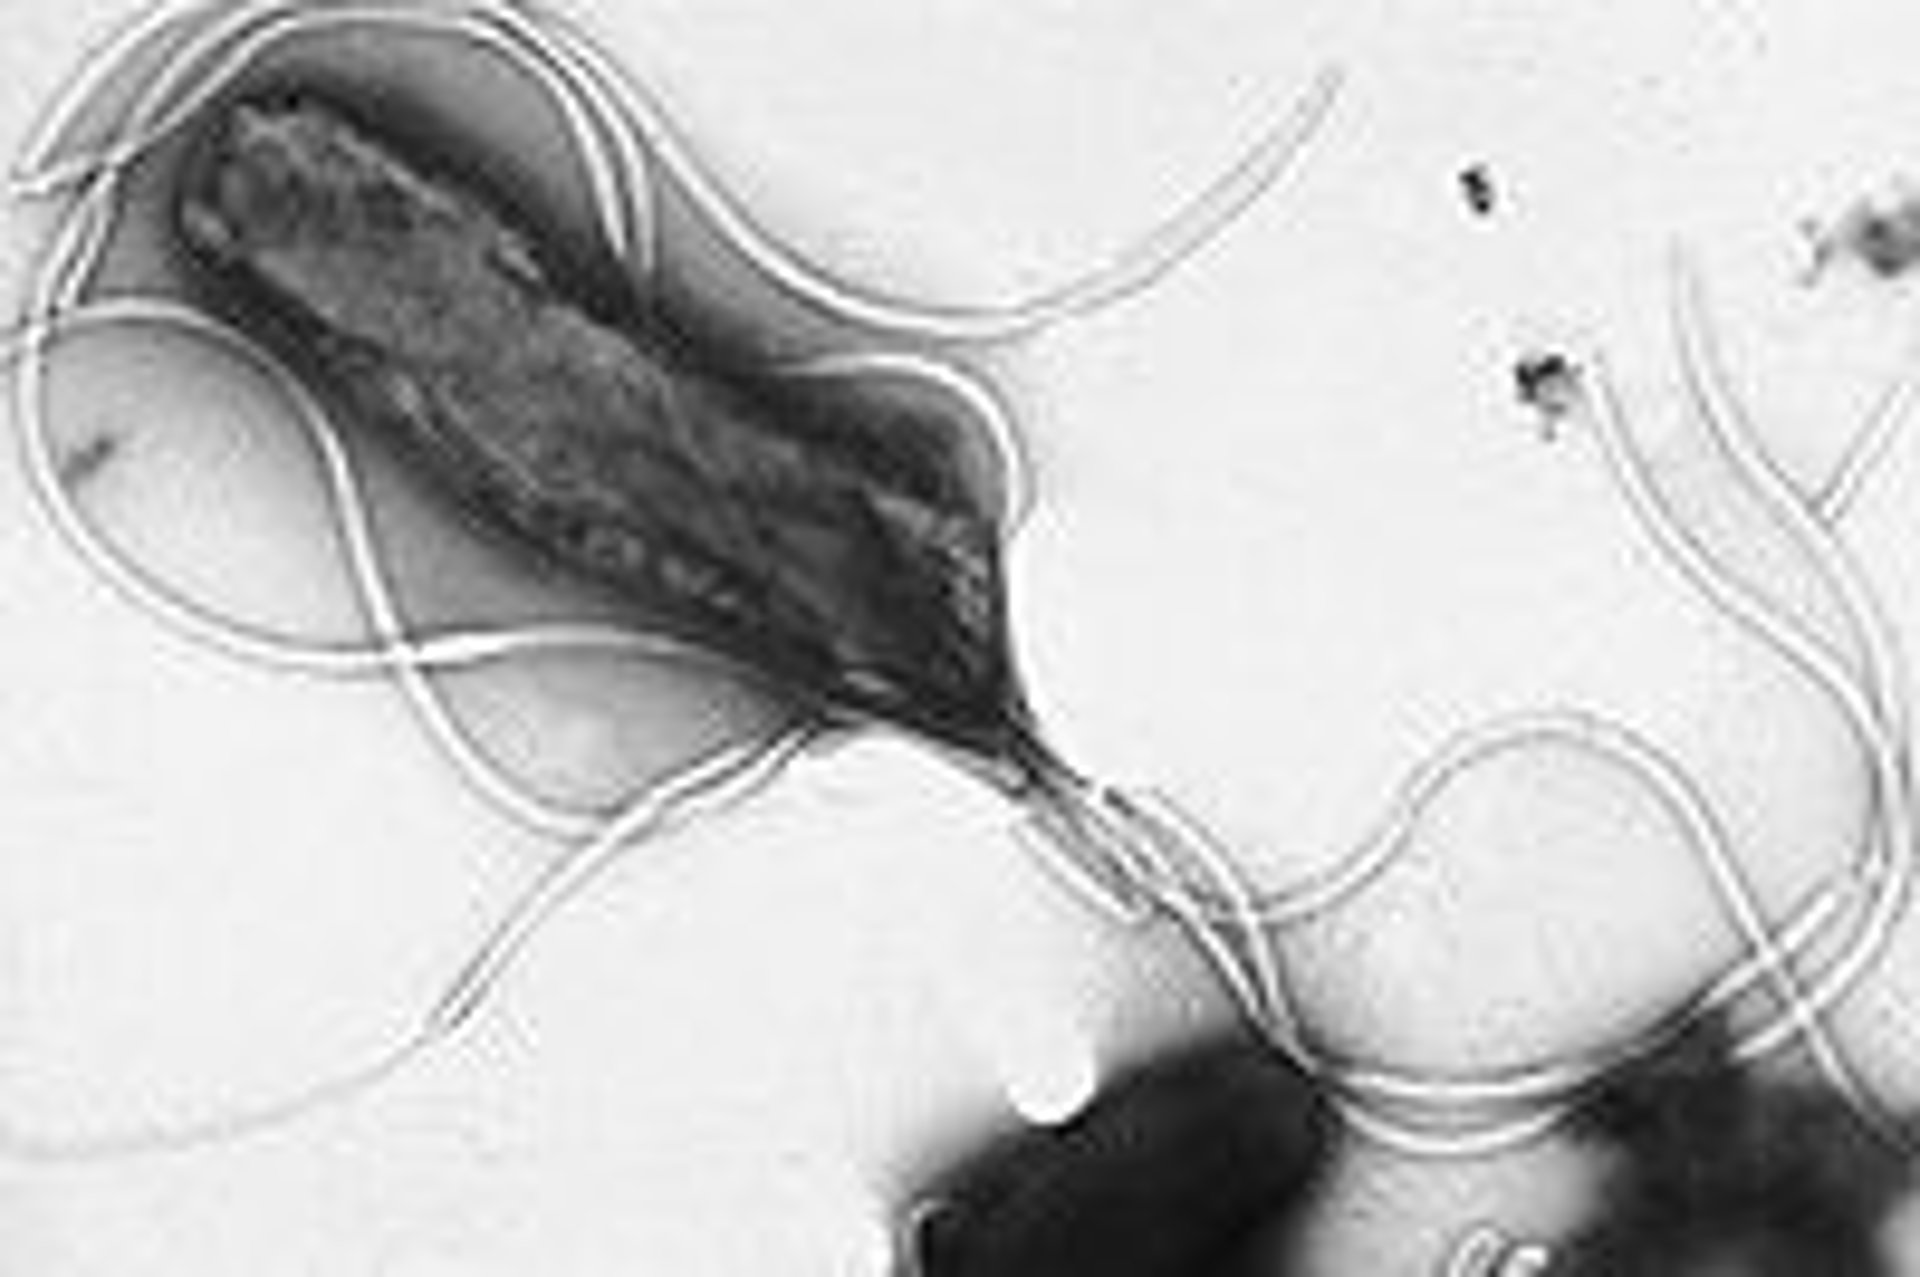

'Helicobacter pylori'

WIKIPEDIA